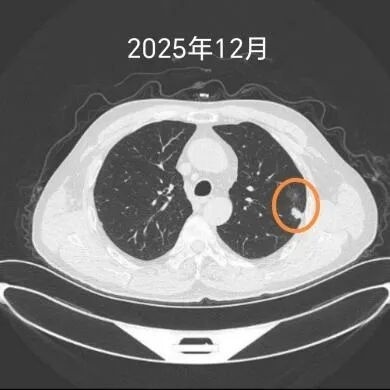

“除了戒烟,还要记得定期复查,有什么不舒服的也能及早治疗。”就这样,在术后两年的复查中,医生发现,杨先生的左上肺又出现了一个明显的实性结节,并有胸膜牵拉表现,提示恶性可能。这让杨先生再次来到该院心胸外科就诊。